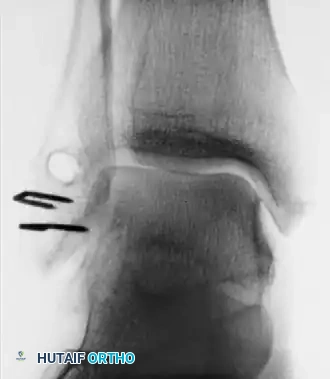

- Stress Radiography: Mechanical instability is confirmed when stress radiographs demonstrate 8 to 10 degrees of increased talar tilt in the ankle mortise compared with the contralateral normal ankle.

- Advanced Imaging: If stress radiographs are negative but pain persists, other etiologies such as stress fractures, osteochondral lesions of the talus (OCDs), or peroneal tendinopathy must be ruled out.

Associated Surgical & Radiographic Imaging